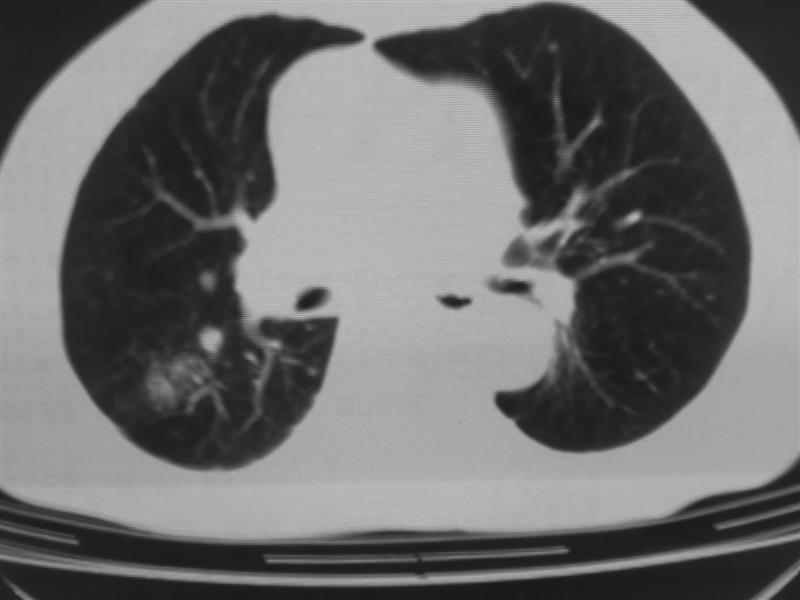

标题: CT10080:F76Y,各位老师发表高见!!! [打印本页]

标题: CT10080:F76Y,各位老师发表高见!!!

支持右下肺癌伴肺内转移

右下肺周围型肺癌伴双肺右侧叶间 胸膜及右肺门淋巴结转移

考虑:肺癌伴肺、胸膜 纵隔淋巴结转移可能性大!